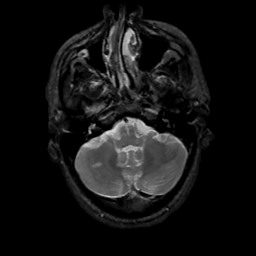

MR Study #13, May 19, 1991 -- Slice #10